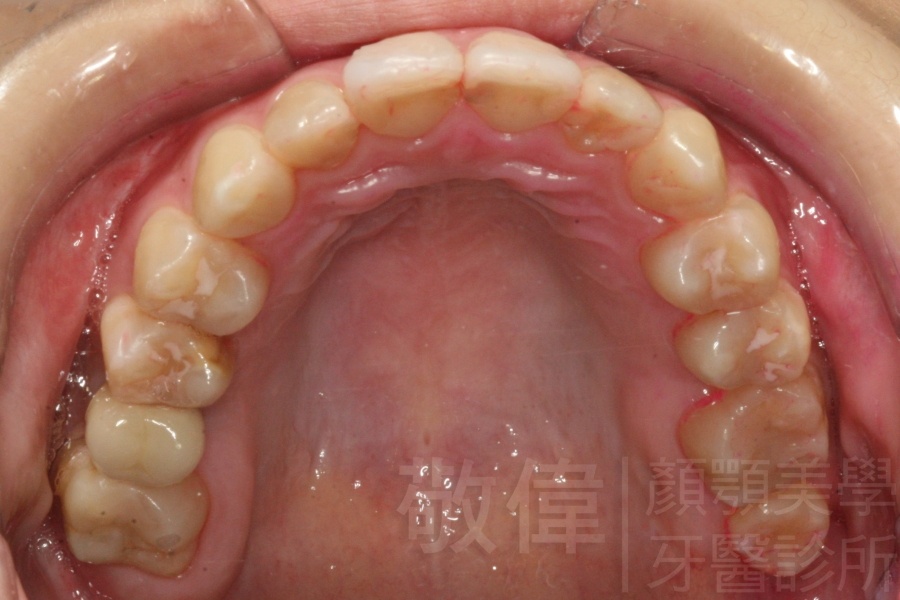

齒顏矯正/戽斗、亂牙、爛牙,變身 免植牙的健牙美女

變臉矯正,原來戽斗妹跟大歪臉變成自信正妹

經由本院3D數影X光影像儀分析、與3D齒顎顏矯正技術,再配合口腔顎面正顎專科醫師施以正顎手術治療,雙方共同合作,使患者臉部外觀有很好的改善,大歪變小歪,產生了天南地北的大改變,她的人生也整個變得不一樣。